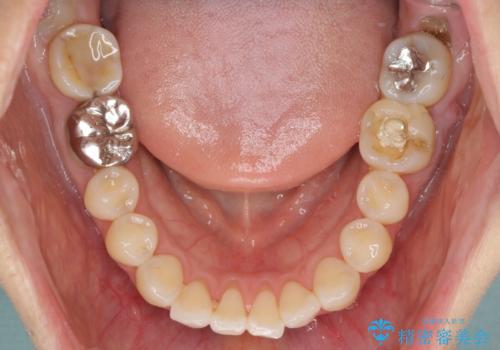

- 捻れた前歯と目立つ銀歯を気にして来院された患者様です。

左下大臼歯は根管治療が必要であったため、矯正治療前に根管治療を行い、その後矯正治療を行うこととしました。

矯正治療後には期にある銀歯を全てセラミッククラウンなどで補綴治療することとしました。

口を開ける度に目立っていた銀歯もセラミックで自然な口元の印象となりました。